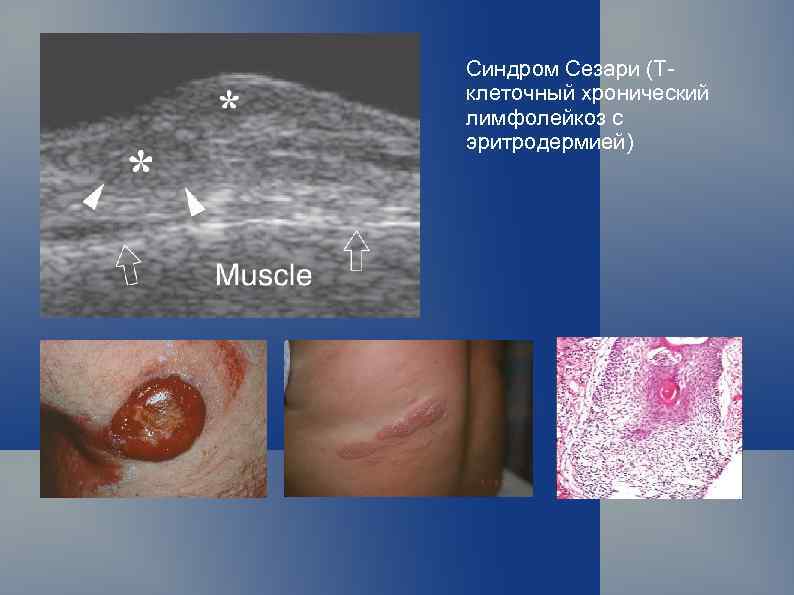

Синдром Сезари (Тклеточный хронический лимфолейкоз с эритродермией)